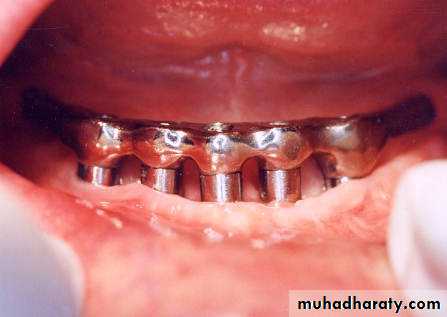

Endosteal or Endosseous implantA. Plate-form implant :

• Blade Implants have a long track record, much longer than the Root form Implants. Their name is derived from their flat, blade-like (or plate-like) portion, which is the part that gets embedded into the bone.

•